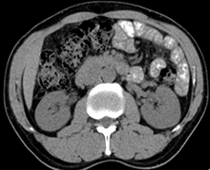

患者,男,57,常年不吃午饭,近一个月来腹部隐痛,无明显黄疸,明天进行增强扫描,图象另上传,麻烦各位帮忙一起看看讨论讨论

肝外胆管扩张,胰头增大,肠系膜上静脉似有包埋征象。

考虑:胰头占位性病变,建议增强进一步检查。

胰头增大,考虑胰头占位性病变。

胰头区占位

胰头增大,胆总管增宽,考虑胰头癌可能性大,明天看增强片有助诊断.